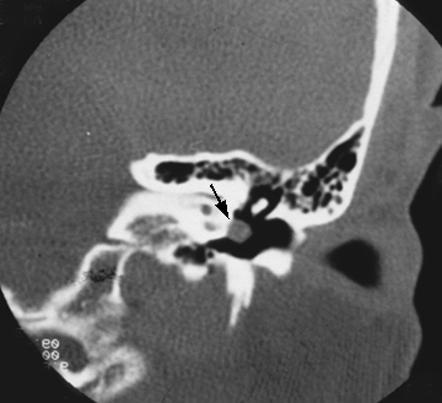

aberrant ICA